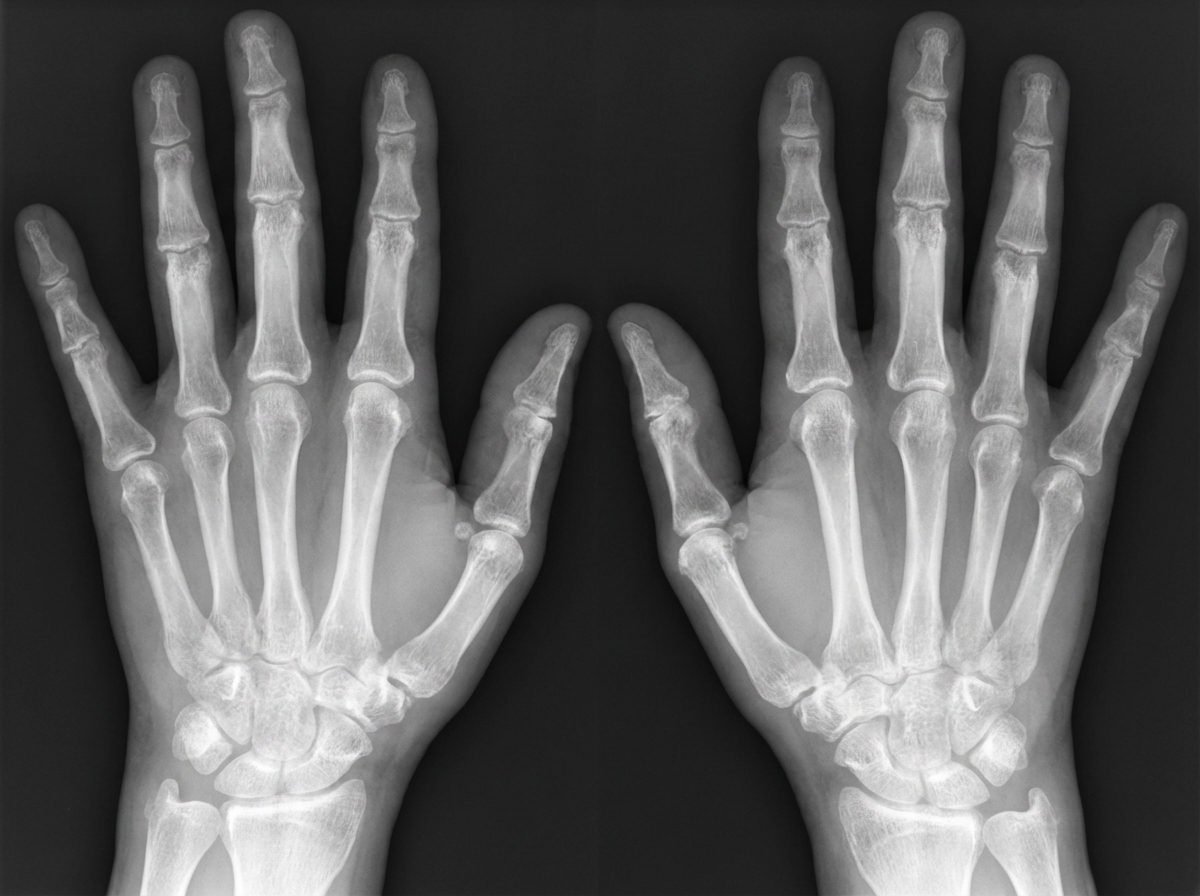

A 42-year-old woman comes to the physician because of a 10-month history of joint pain and stiffness in her wrists and fingers. The symptoms are worse in the morning and improve with activity. Physical examination shows swelling and warmth over the MCP and wrist joints in both hands. An x-ray of the hands is shown. Synovial biopsy from an affected joint would most likely show which of the following?